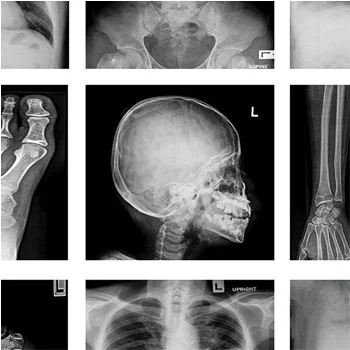

Catastrophic injuries can affect many areas of the body. They can occur for a variety of reasons, including car accidents and distracted driving. Catastrophic injuries will keep you out of work, sometimes for life, taking a huge financial toll on you and your family. Attorneys Richard R. Kennedy and Richard R. Kennedy III can help you recover your lost wages, as well as the money needed for your medical bills.

A traumatic brain injury is usually the result of a hard blow to the head. The resulting damage will not only affect a victim’s physical health. It will also impact his or her cognitive function, critical thinking, and personality. If your loved one is not able to file a lawsuit, a guardian, spouse, or parent can typically do so on his or her behalf.

A spinal cord injury can affect the nerves, discs, and vertebrae along any part of your spine. Damage to the spinal cord can cause a significant loss of mobility. You or your loved one may be facing the costs of emergency treatment, rehabilitation, and even long-term care. We will provide the compassionate yet hard-hitting representation you need.

Neck and back injuries can affect a large portion of your body. Pain may radiate into your shoulders and limbs. You may be unable to work or perform routine tasks. Neck and back injuries are not always apparent immediately after an accident. If you begin to experience unusual symptoms in the wake of an incident, we can fight for your rightful damages.

Paralysis can be a catastrophic injury that affects the injured party, their family and loved ones. The inability to use and move various limbs such as the hands or legs can mean extensive rehabilitation, medical expenses, and extreme hardship for everyone involved.

Losing a limb can impact your ability to perform daily routines and essential job functions, affecting your quality of life. This injury can result from an accident, infection, or medical malpractice. If another’s negligence contributed to your injury, we can secure compensation for your hardship.

Bone fractures are caused by extreme pressure or force of impact, and can result from a car accident, slip and fall incident, workplace accident, or contact sports. Depending upon the location and extent of the fracture, victims may incur significant medical expenses and require ongoing care.